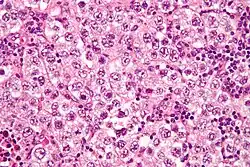

Micrograph of a seminoma, a common germ cell tumor.

Germinoma (including dysgerminoma and seminoma) 40–50 Malignant Sheets of uniform polygonal cells with cleared cytoplasm; lymphocytes in the stroma About 10% have elevated hCG